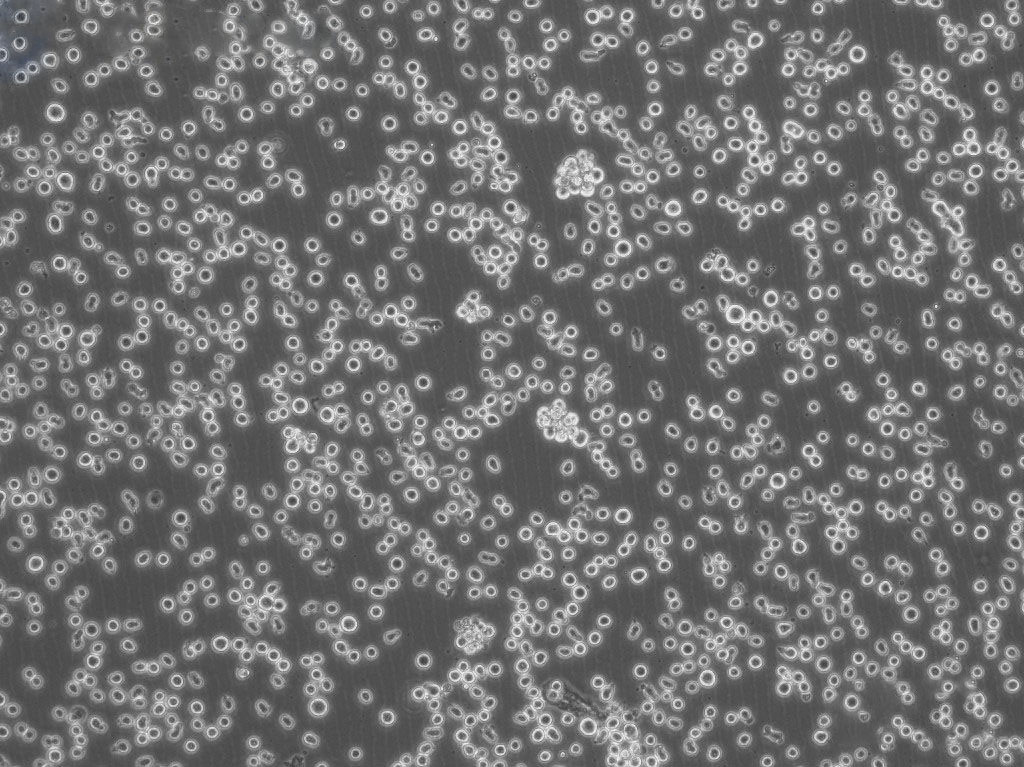

A20 小鼠B细胞淋巴瘤细胞系

细胞背景资料:淋巴瘤;BALB/cAnN

细胞形态:淋巴母细胞样

细胞生长:悬浮

细胞生长特性:悬浮